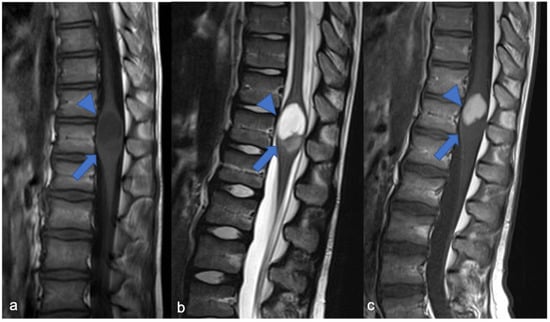

3. Ependymomas